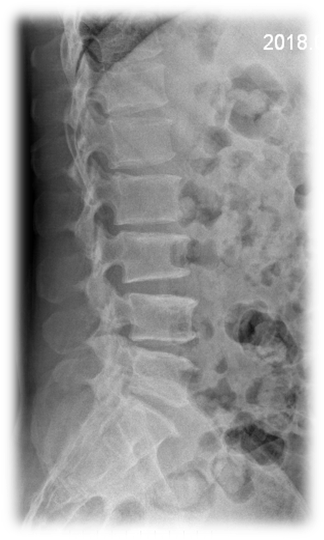

术前 图片2